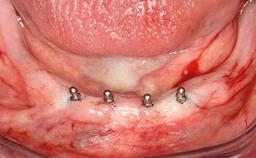

Mandibular Overdenture Supported by a CAD/CAM-milled Bar with Long Distal Extensions on Two Conventionally Loaded Implants

# of Implants 2

Type of Implants One-Piece

Defining Characteristics Fully edentulous lower jaw to be rehabilitated with two or more implants

Modality 2 interforaminal implants